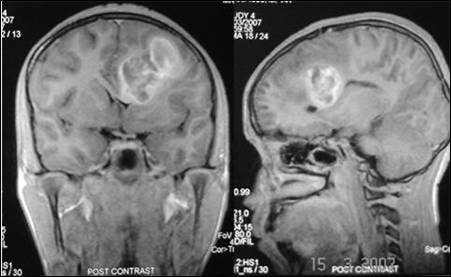

Figure 2: Contrast MRI coronal and sagittal sections

showing more details of the lesion; note the mass effect and distortion of

corpus callosum.

investigations were normal. He was investigated with magnetic resonance imaging

(MRI) which showed evidence of left basal ganglionic haematoma with mass effect

and midline shift (Fig. 1,2). He underwent left